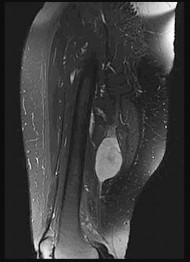

This patient has a dedifferentiated liposarcoma within a preexisting atypical lipomatous tumor. The imaging demonstrates a large fatty mass with increased internal septations proximally (the atypical lipomatous tumor) and a solid enhancing mass distally (the dedifferentiated portion). A biopsy reveals a high-grade liposarcoma. The other diagnostic responses do not reflect sarcomatous transformation of the lesion.

Surgical treatment of a high-grade sarcoma involves wide surgical resection. Radiation decreases local recurrence but does not clearly influence overall survival. The role of chemotherapy in high-grade soft-tissue sarcomas remains investigational; there is a modest (8%-15%) associated improvement in overall survival.

Intramuscular lipomas and atypical lipomatous tumors are treated with marginal resection alone. Radiation therapy for soft-tissue sarcomas may be given before or after surgery. When administered before surgery, patients have a higher wound complication rate but better long-term function attributable to lower rates of lymphedema, fibrosis, and contractures.